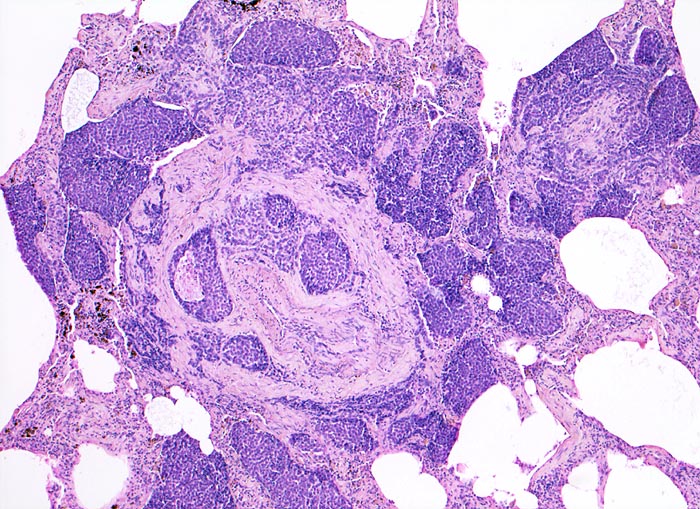

Morphologische Merkmale:

• Sternförmiges Karzinom mit zentraler Vernarbung mit reichlich schwarzem Anthrakosepigment.

• Das Karzinom ist aufgebaut aus tubulären und kribriformen Drüsen.

• In den sternförmigen Ausläufern finden sich erweiterte Endothelausgekleidete Lymphgefässe in der Nachbarschaft von Blutgefässen.

• Die erweiterten Lymphgefässe enthalten solide Tumorzellaggregate.

• Vermehrte Alveolarmakrophagen in den peritumoralen Alveolen mit phagozytiertem Anthrakose- und Hämosiderinpigment (Rauchermakrophagen).

• Peritumorales Lungenemphysem (Traktionsemphysem).